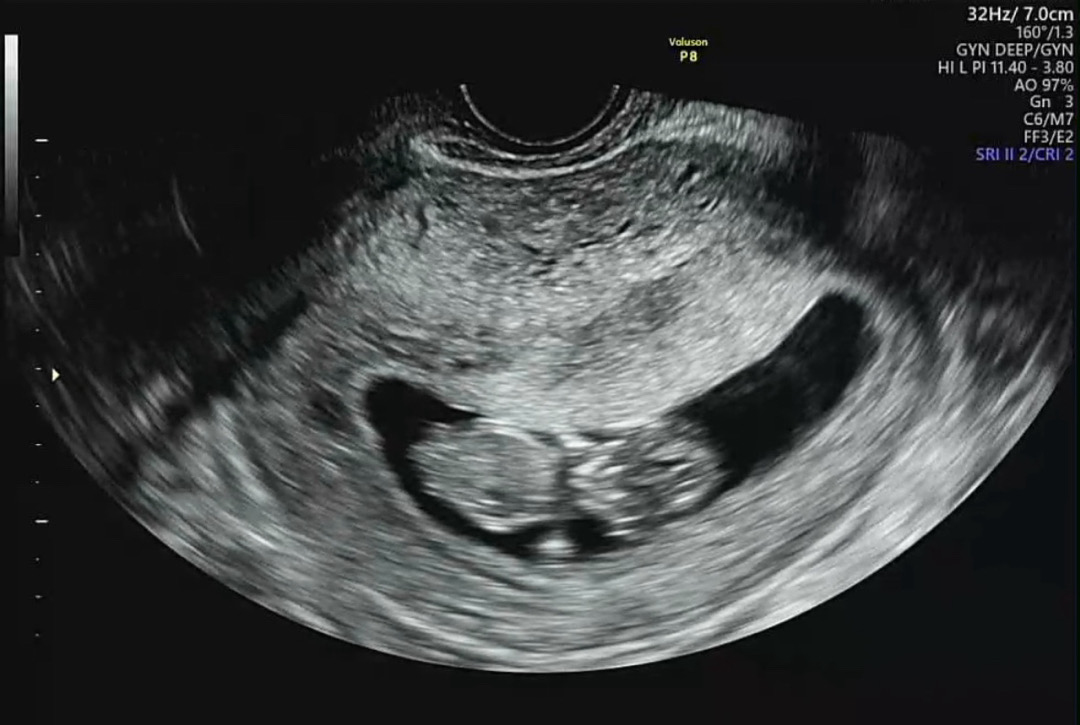

11주0일 성별이 보일까요???

11주 0일 방금 찍은 초음파입니다 이 시기엔 성별이 보이나 궁금하고 양수가 적은데 좋은 노하우 있으면 알려주세여!!